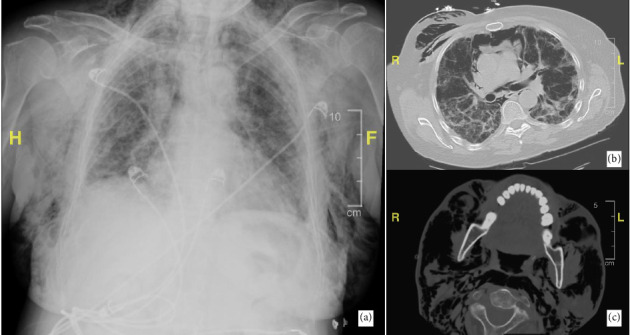

Antimelanoma differentiation-associated gene 5 (MDA5) dermatomyositis (DM) is a subtype of DM associated with characteristic mucocutaneous features. These individuals have an increased risk of developing interstitial lung disease (ILD) that ultimately leads to a complicated clinical course. Certain clinical findings suggest anti-MDA5 positive DM over anti-MDA5 negative DM, including cutaneous ulcers, diffuse nonscarring alopecia, and panniculitis. ILD and pneumomediastinum are known to be two of the most important pulmonary complications of anti-MDA5 DM because of the possibility of a rapidly progressive course and poor survival. This case outlines the unique presentation of pneumomediastinum, subcutaneous emphysema, and ILD in a patient with anti-MDA5 positive DM.